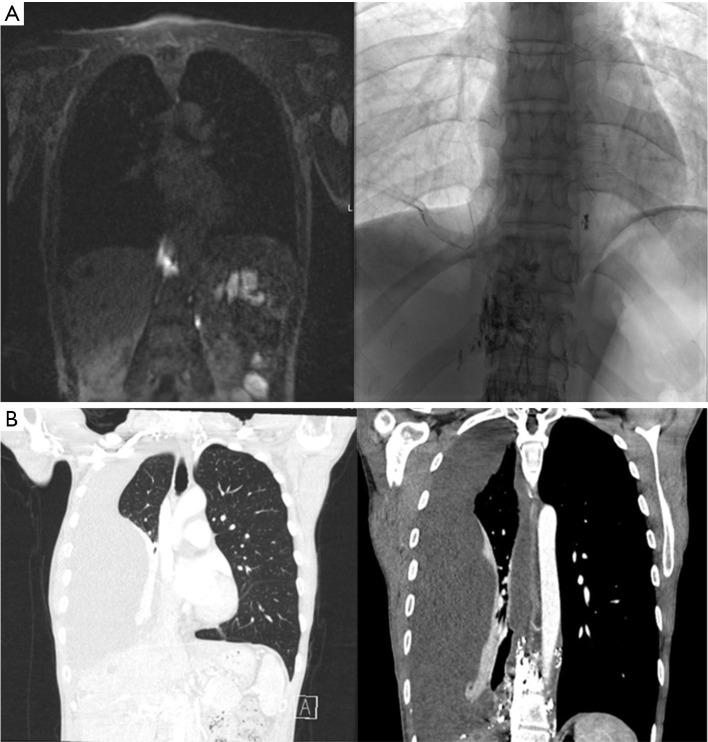

A 50-year-old female with a recent history of coronavirus disease (COVID)-19 presented with shortness of breath. She was found to have a right pleural effusion and was admitted to the hospital, where a chest tube was inserted and pleural fluid analysis confirmed the diagnosis of a chylothorax. Conservative management was attempted but with little success. Initial magnetic resonance lymphangiogram (MRL) revealed abnormal enhancing lymphatic masses in the right paraspinal thoracic space as well as lympho-venous junction obstruction with large neck collaterals. She then underwent percutaneous lympho-venous junction angioplasty followed by multiple rounds of glue embolization without clinical improvement. The decision was then made to proceed with a thoracotomy, identification of the site of thoracic duct (TD) leakage, and a mechanical pleurodesis assisted by intraoperative imaging. Ten mg of ICG was injected into the inguinal lymph nodes. Using a camera capable of detection of near-infrared (NIR) light, we were able to visualize the site from which the ICG was extravasating in the chest. Glue was then injected in that area to further help in reducing the leak. After keeping her nil per os (NPO) and requiring one more ligation, a repeat MRL showed a markedly decreased leak into the right pleural space. Two weeks later, she was seen in clinic and reported significant improvement in her symptoms.

This is the case of a 50-year-old female who was found to have a significant right chylothorax. She underwent conservative management, followed by tube thoracostomy, and TD ligation but was refractory to treatment. Fluorescence-guided surgery was pivotal to localize the leakage site and help seal it intraoperatively.